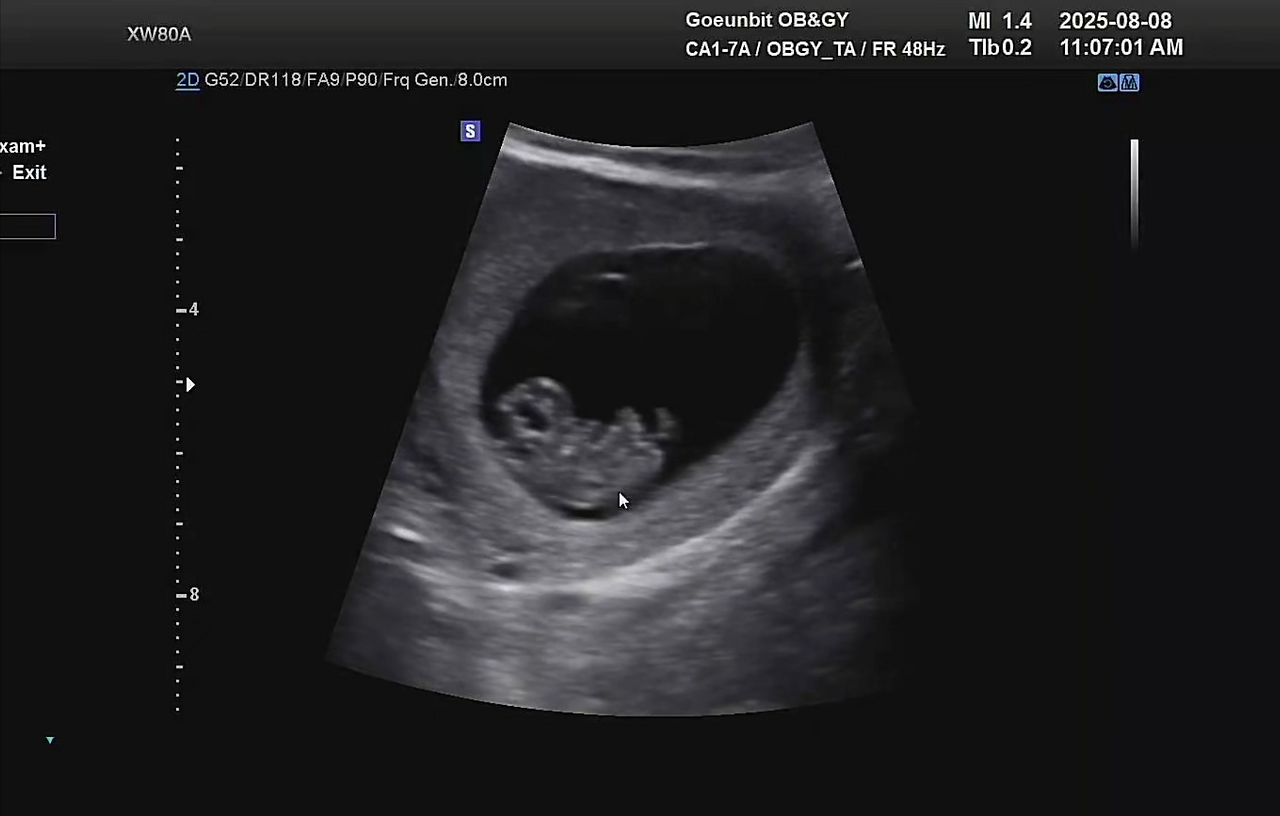

2주 만에 병원에 가서 배로 초음파를 봤지만, 느낀 건 “아직 잘 있구나” 하는 안도감뿐이었다.

내 눈에는 여전히 희미한 그림자일 뿐, 다른 산모들이 보여주는 귀여운 젤리곰은 보이지 않았다.

10주 차